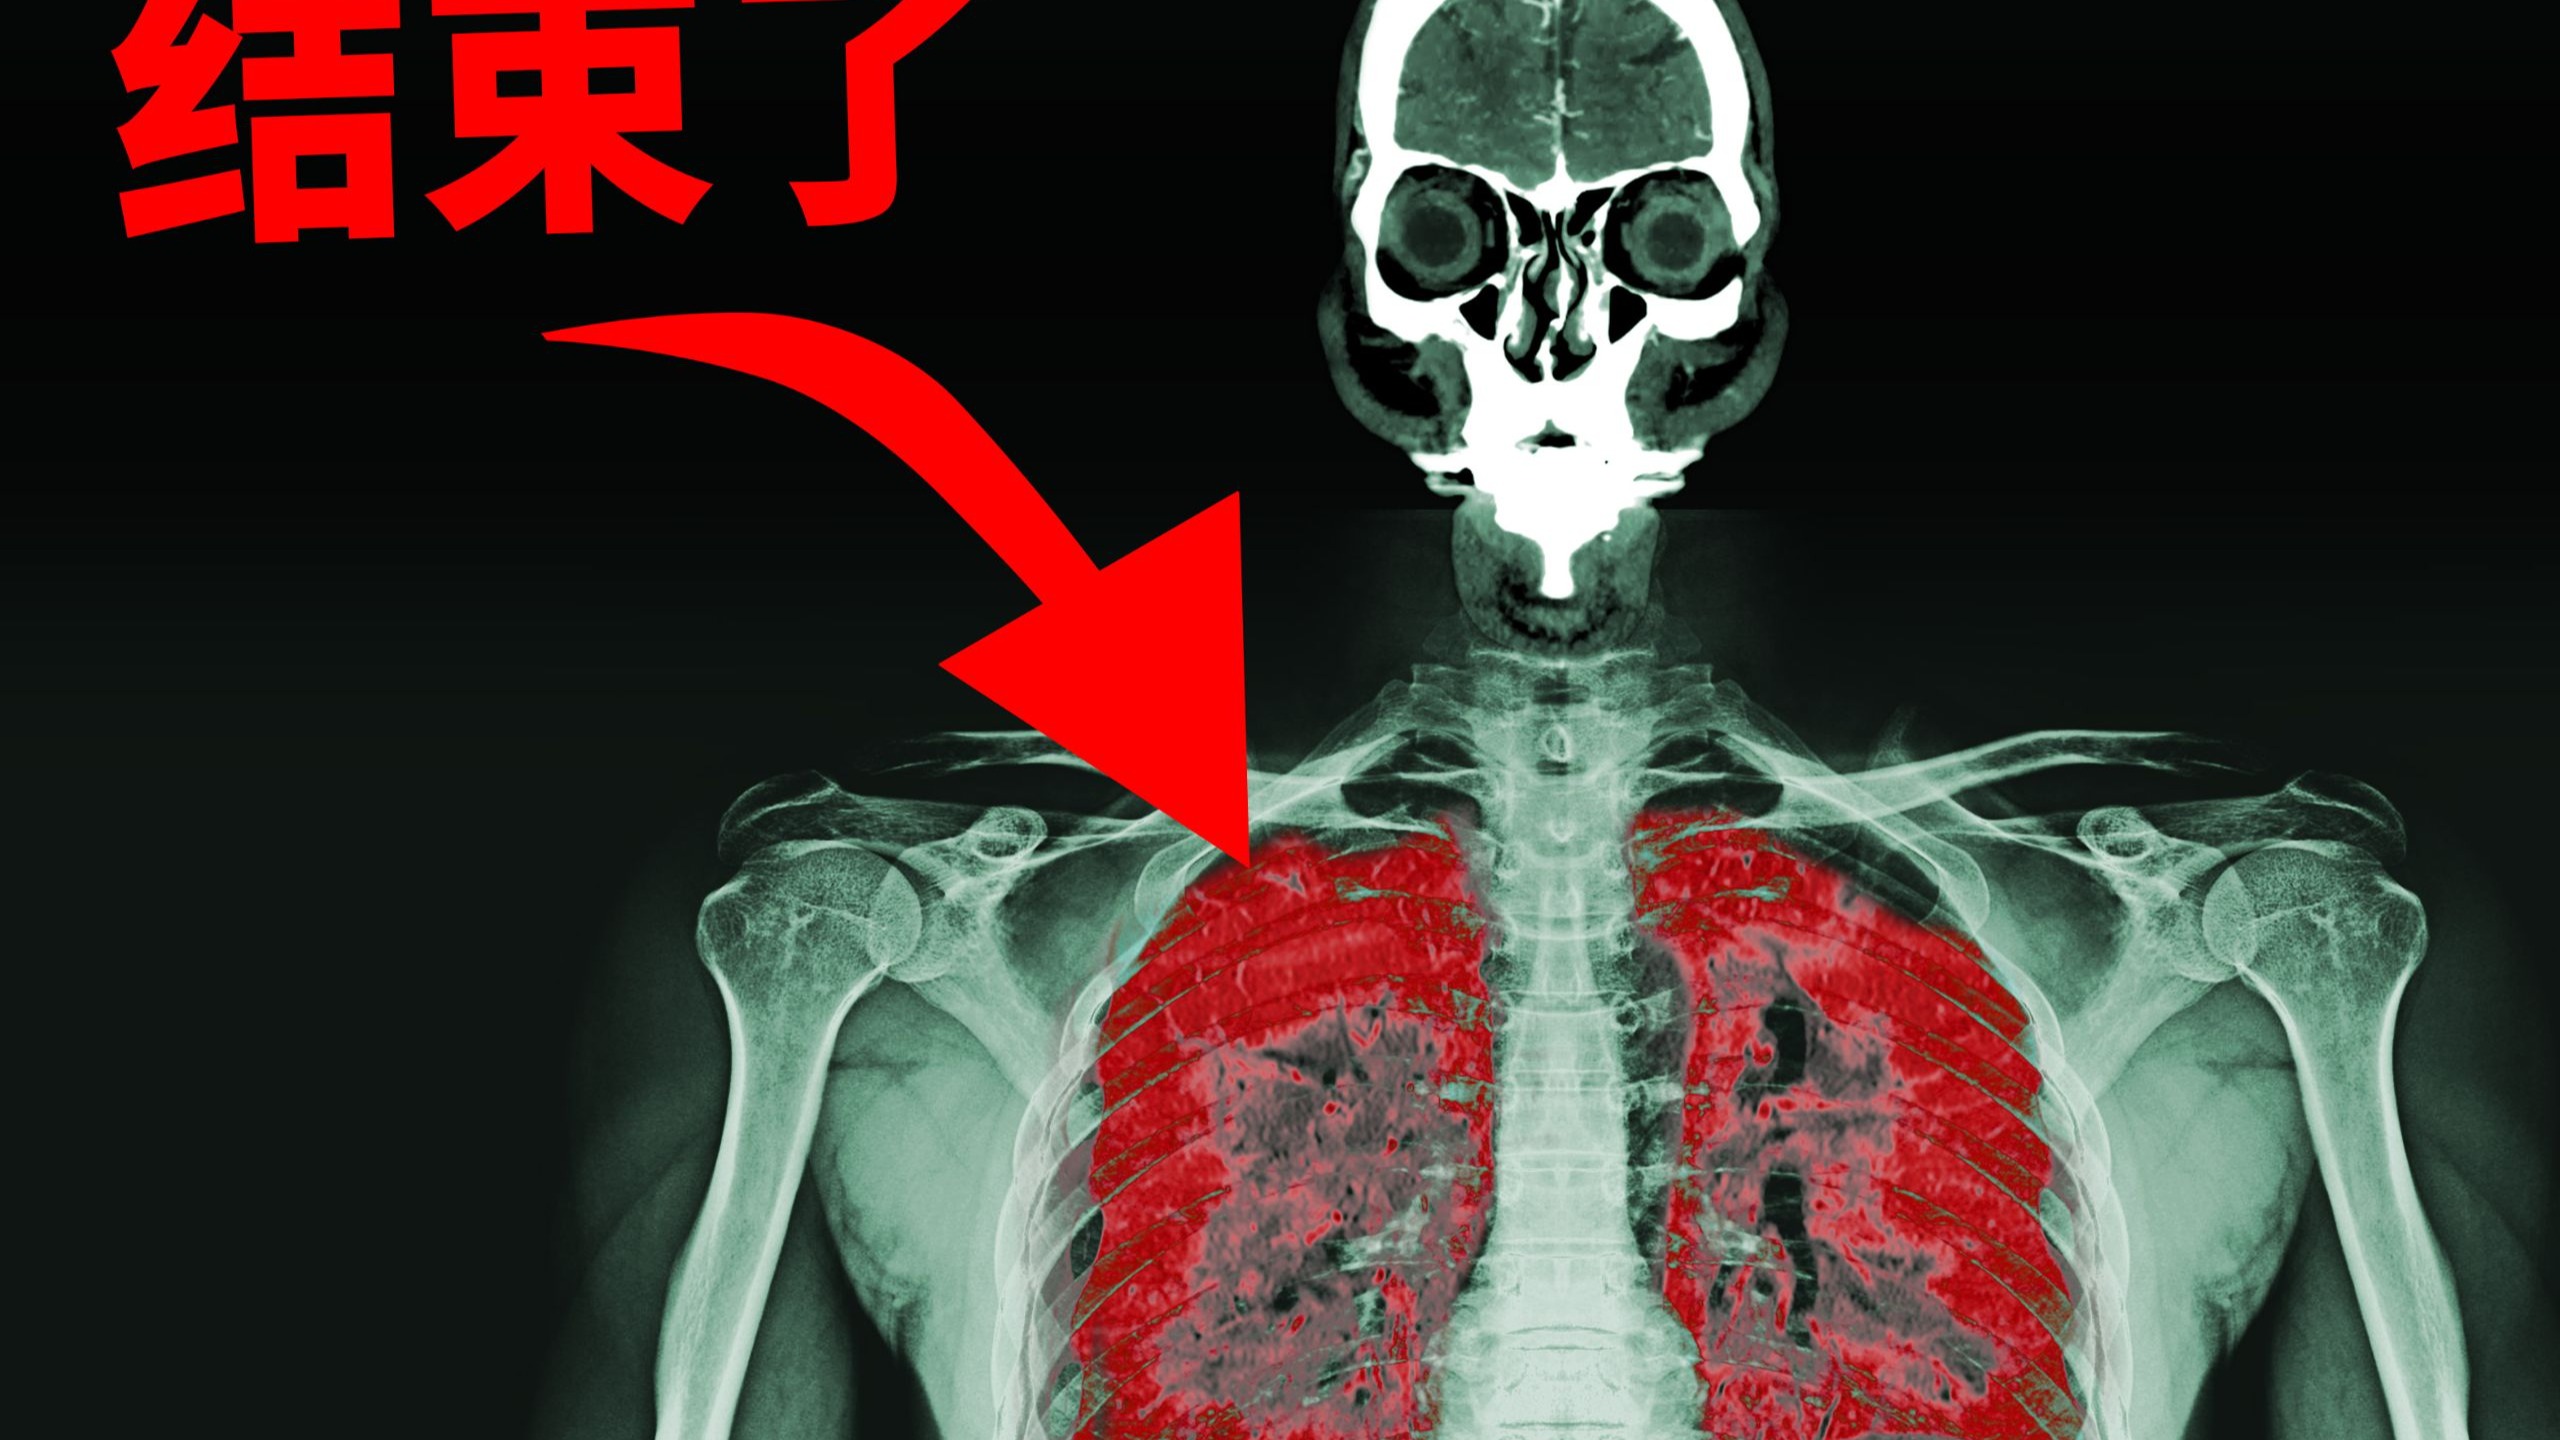

一位小伙子在焊接时不慎合成了“化学武器”,这是他的身体发生的变化